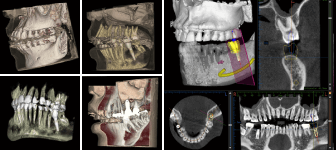

広範囲の撮影が可能なCT(3D撮影)機器です。3D撮影によって多角的な診断が実現し、親知らずの抜歯やインプラント治療、根管治療などの複雑な治療を安全・正確に行うことができます。デジタル方式を採用しているため低被ばくで、被ばく量は従来の機器と比べて大幅に減少しています。

歯科用CT(3Dレントゲン)撮影